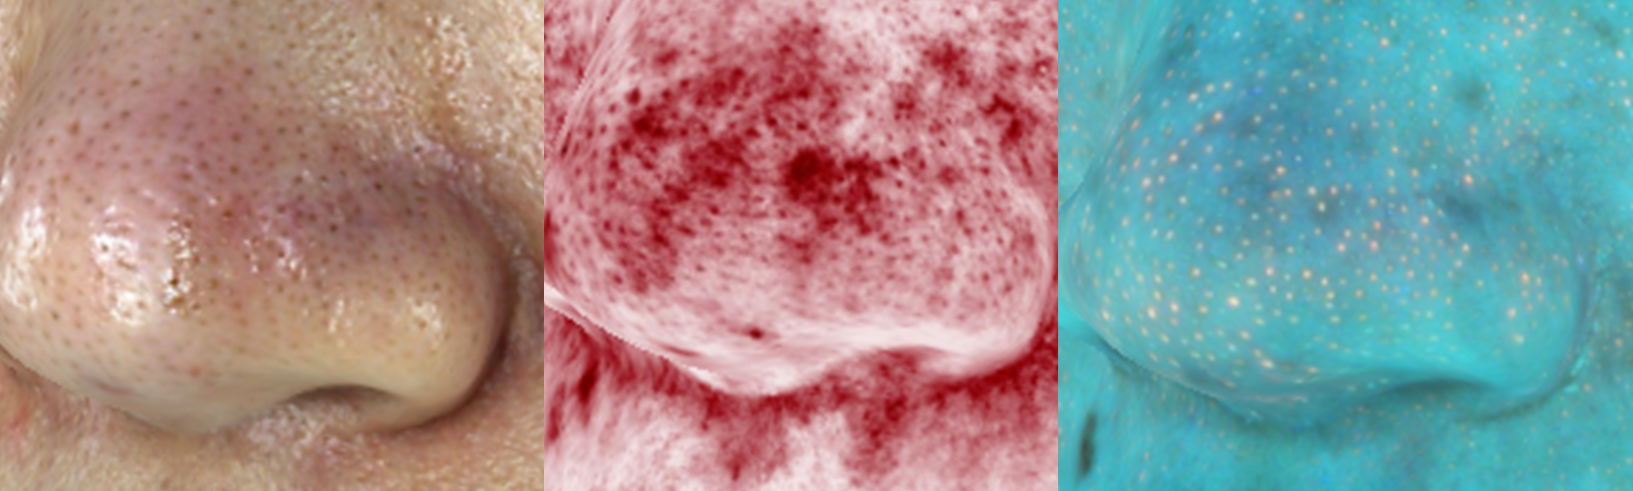

2、黑头粉刺

毛孔中的黑色小点,有明显开口,可挤出黑色角栓;形态为圆形,嵌入毛孔内;颜色为黑色或暗褐色;大小直径一般1-3毫米

影像图切片